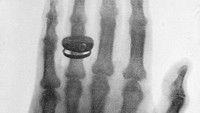

Foto rontgen ini diklaim sebagai foto sinar-x pertama yang dibuat oleh Profesor Konrad Roentgen pada tahun 1898.